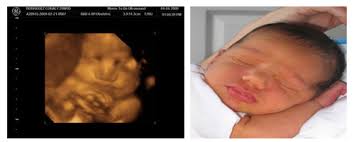

These before and after images are from actual 3d/4d ultrasound sessions performed at pregnantsee!you will enjoy the same view of your little one and even see full motion video of your unborn baby. 18 week hd live/4d ultrasound. Ultra sound beim führenden marktplatz für gebrauchtmaschinen kaufen. Full service 3d/ 4d ultrasound photography studio. Feb 9, 2015 at 8:07 pm. The only difference is that with the 5d, you can obtain sharper and better resolution images. It is fully formed and mostly filled out. It is a fun time for the ultrasound as many times you will see movements like smiling, eyes blinking, hands moving, and many other movements.

The baby has had time to build up body fat, but still has room to move around. Plus, learn about the major reproductive developments at this stage. 3d/4d ultrasounds sessions should be remembered as good memories for years to come. A 3d/4d ultrasound taken of a baby that visited prenatal impressions, the only premier provider of 3d/4d ultrasounds in orlando, florida since 2005. It was a very special day for my husband and i.